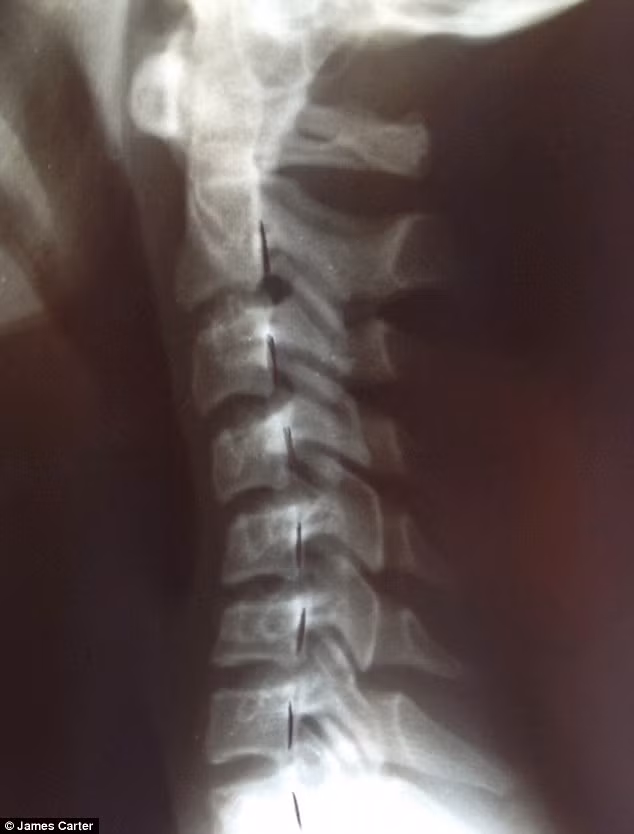

Đây là hình chụp X -quang xương sống của một thiếu niên 20 tuổi nghiện smartphone, tình trạng xương sống thoái hóa tương tự như một cụ ông 80 tuổi.